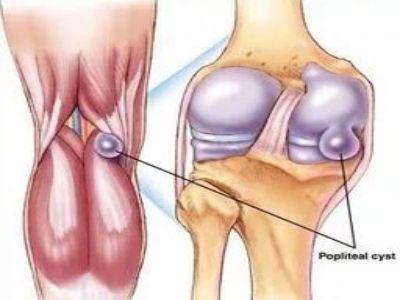

腘窝囊肿

腘窝囊肿,大多属于一种良性的关节内囊性肿物,囊内往往为关节液。症状主要是膝关节后方感觉疼痛和紧绷发胀,严重者也会导致膝关节的屈伸受限。现早期可以无压痛,但一般有波动感,B超、X光片可以看到在腘窝有一个类似球形的软组织阴影。腘窝囊肿一般如果没有不适症状可以不用处理,对人体没有什么危害。如果囊肿较大,已经引起不适症状往往需要进行治疗。一般分为关节穿刺抽吸和手术切除治疗,但在治疗前一定要诊断明确,如果腘窝囊肿是因为其他关节疾病引发,不论抽吸还是手术切除,都容易导致复发,所以找到引起腘窝囊肿的原发病很重要。